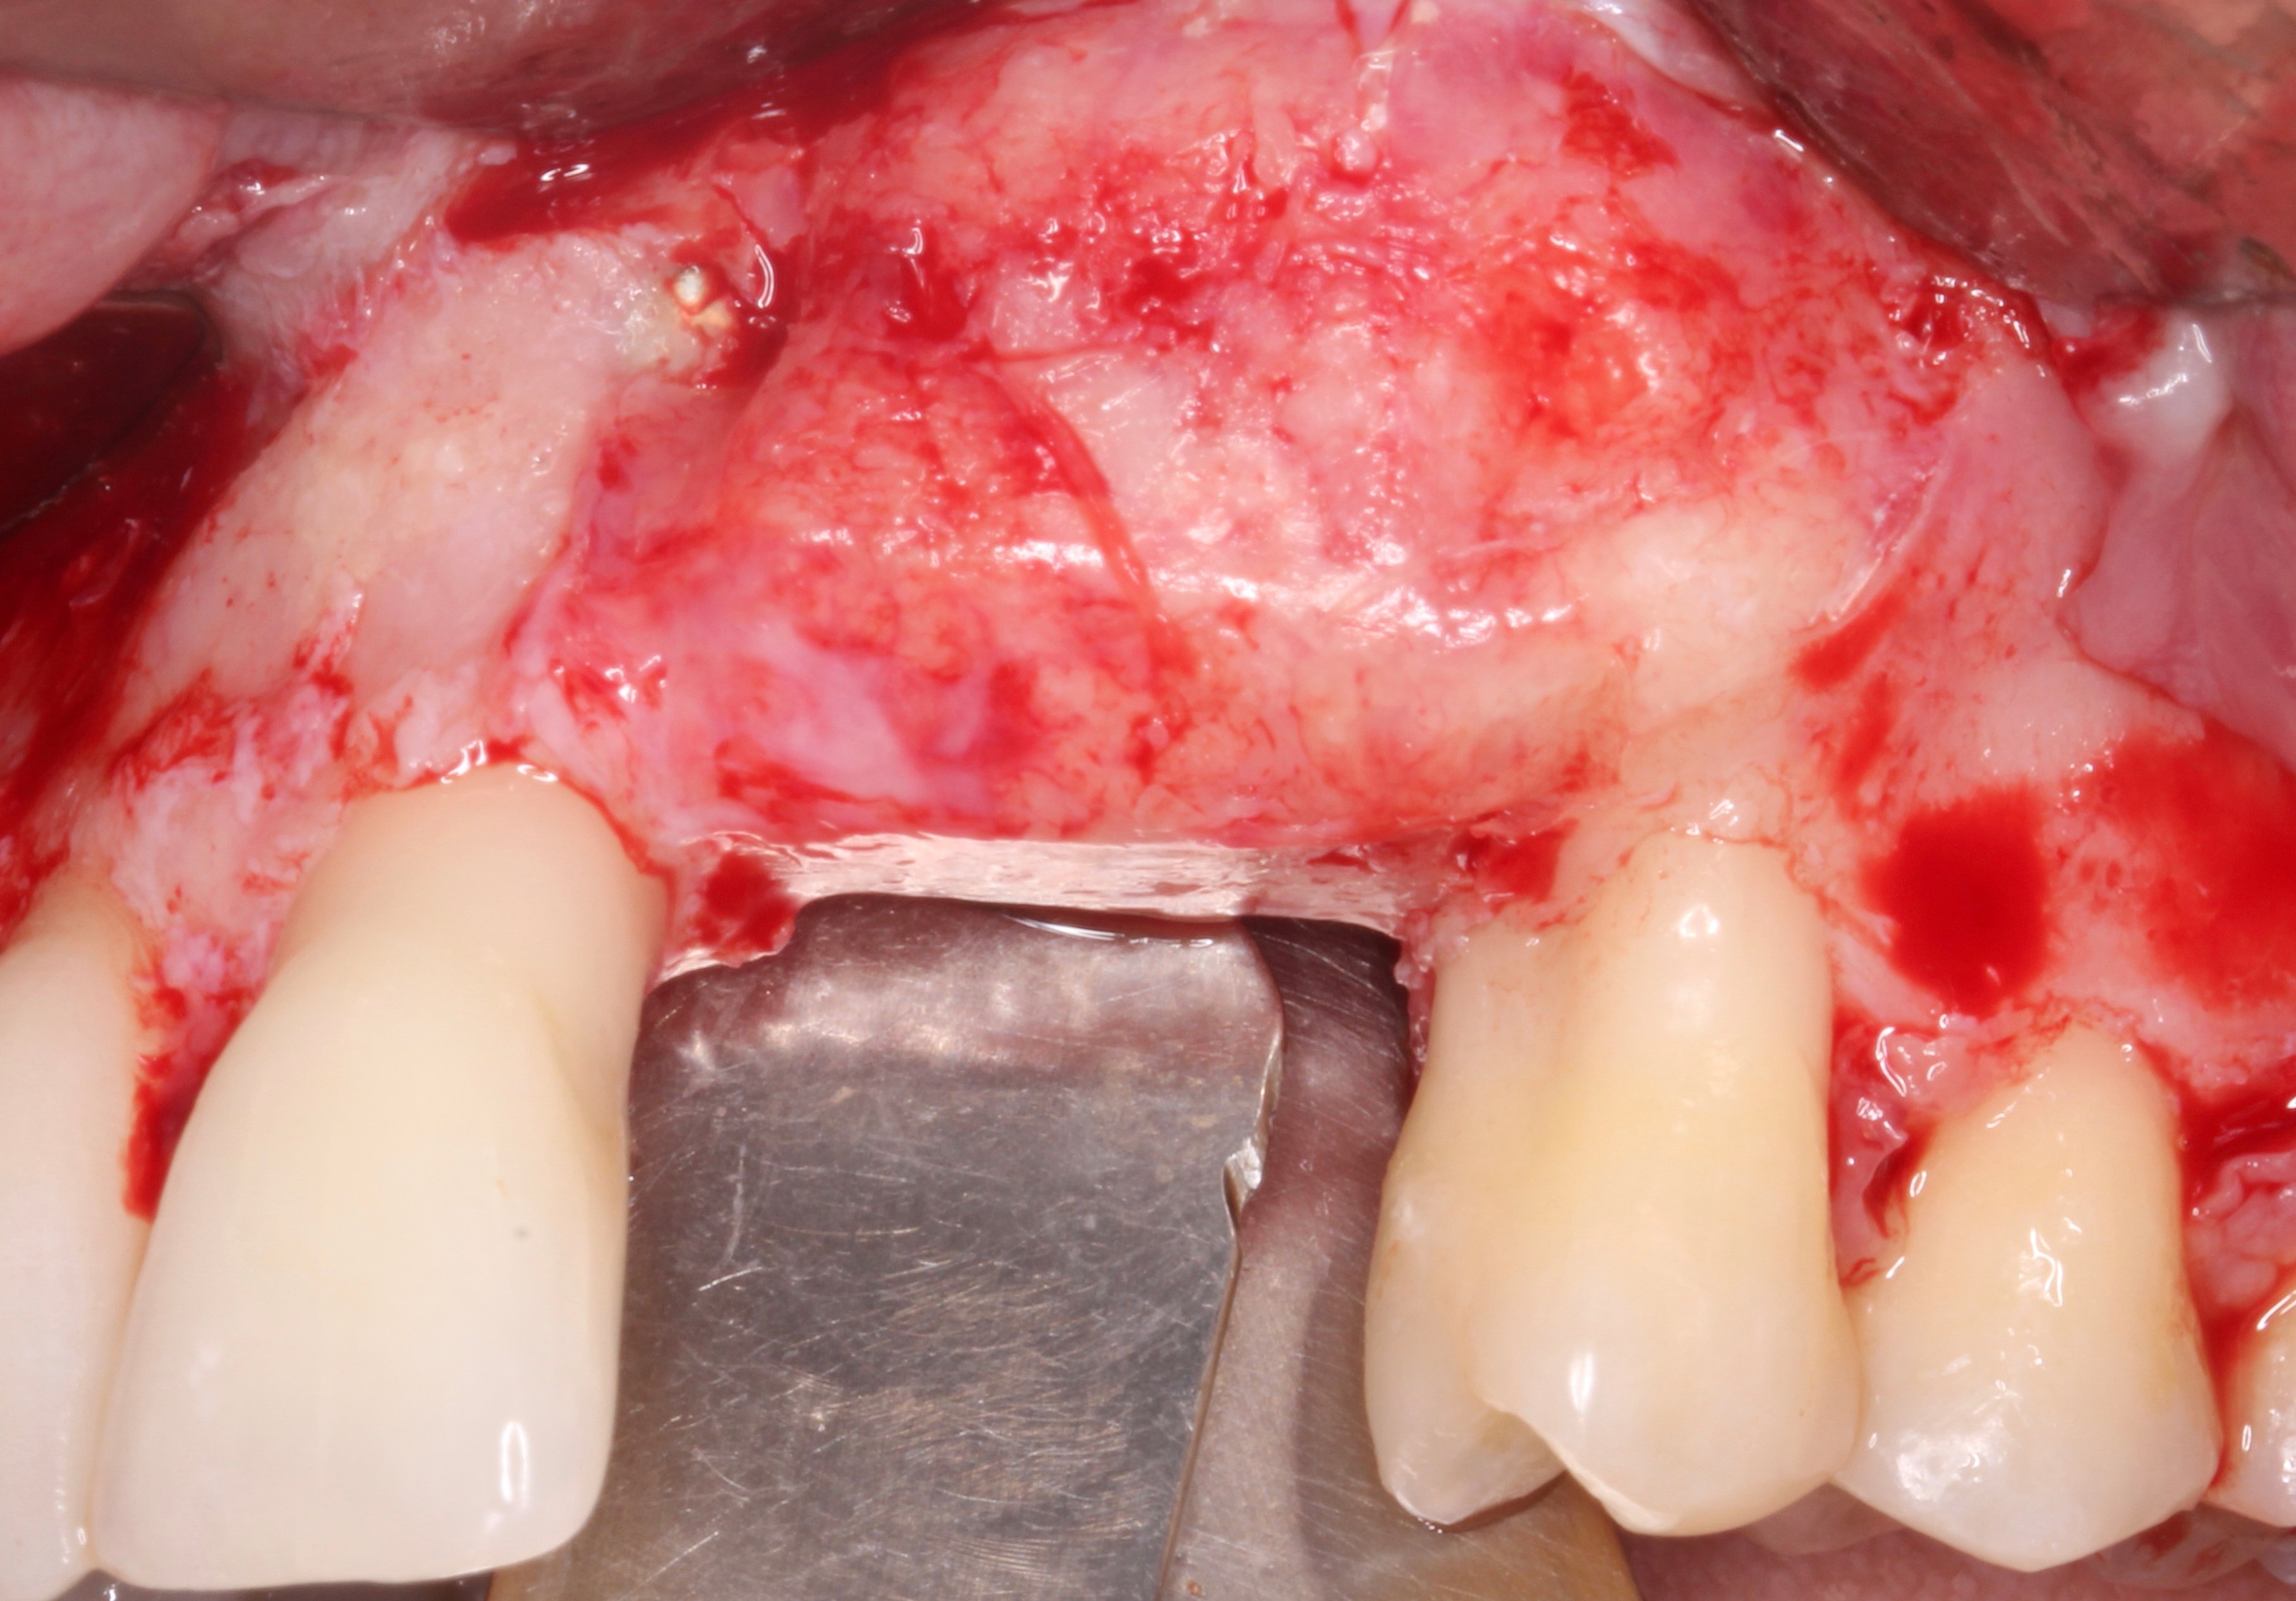

- 3 months later: (which turned out to be 2 years later because the patients was treated and failed elsewhere): 3D guided bone regeneration using 100% autogenous bone and a PTFE, Ti-reinforced NeoGen® membrane which was fixed by Neoss Tacks.

Step by step

Figure 1.